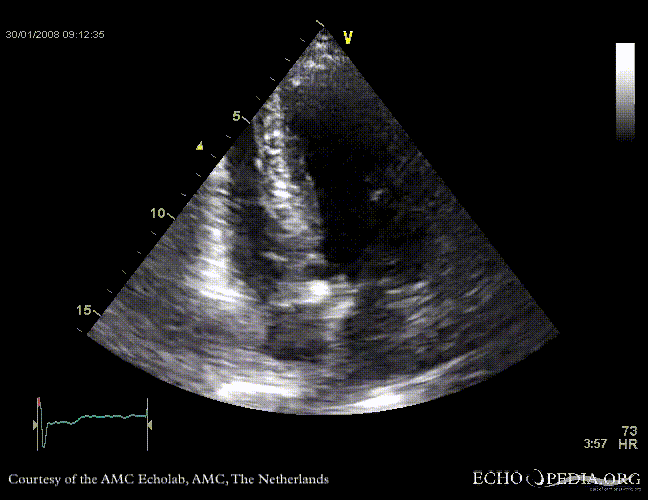

Aortic valve stenosis

AoS3